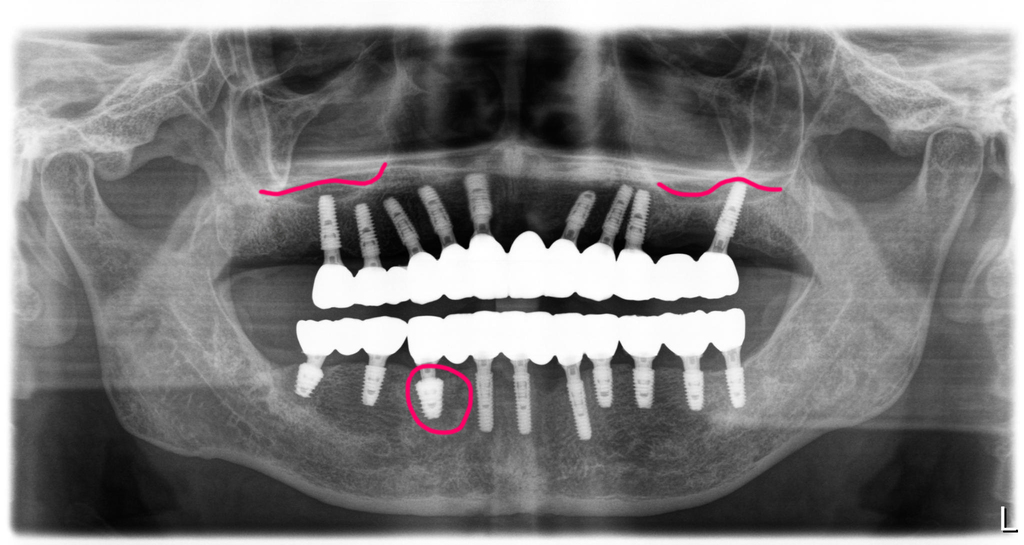

잇몸질환(치주염)이 심한 전체임플란트 사례의

치료전 엑스레이

전체임플란트 치료전후

파노라마 비교

치료전 파노라마 상에서 심하게 치조골이 파괴된 자리인 왼쪽 위 작은어금니 부분은 임플란트를 심지 않고 연결하는 방식으로 처리했구요. 위쪽 어금니부분에는 간단한 상악동 이식술을 시행했습니다. 아래 오른쪽 송곳니부분에도 뻐이식이 진행되었어요. 이렇게 발치와 임플란트식립, 뼈이식이 모두 하루에 진행이 됩니다. 저는(이한나원장) 수천명의 전체임플란트 치료 사례를 시술했으며, 손이 빠르고 정확해서 수술시간이 빠릅니다. 수술시간이 빠르면 경과도 좋고 환자도 덜 힘듭니다.